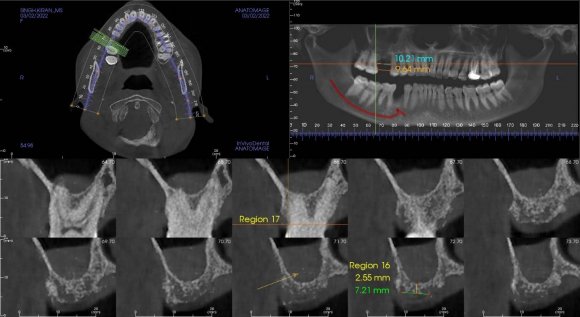

Case report 1 A female aged 29 presented with the complaint of missing teeth in her upper right back tooth region for 3-4 years and desired the replacement of the same. Her CBCT revealed an enlargement of the maxillary sinus with a bone height of 2.55 mm at the desired site (Figure 1). Therefore, a sinus lift procedure using the lateral approach was indicated before implant placement and we accomplished it with the help of the LAS kit.